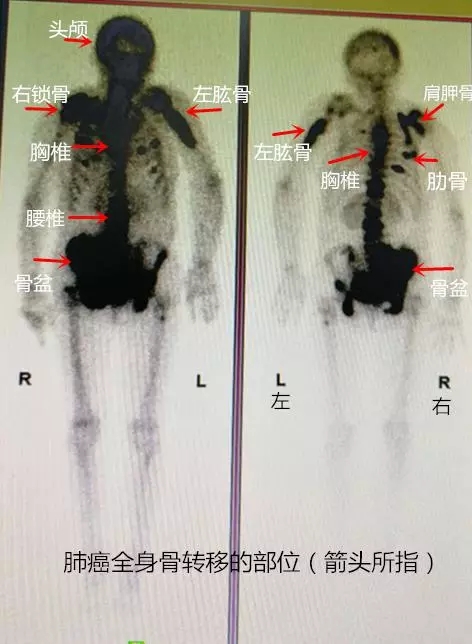

再对其全身进行全身骨扫描(SPECT)检查后发现:其头上,右肩膀上,腰上,背上都存在肺癌的骨转移(如图)。